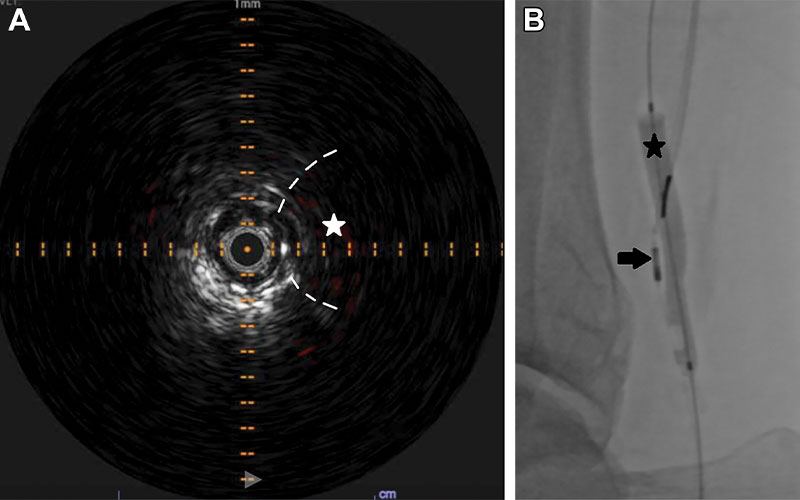

Advances in intravenous ultrasound (IVUS) catheters have opened more possibilities. While single-element, slower- emitting catheters produced images that were often contaminated by electronic noise and wedge-shaped defects in the field of vision, the newer generation allows concentric placement over a guidewire channel with less rigidity, reduced noise and high frequencies, producing crisp circular images across a wide range of diameters.

IVUS offers high-detail images of acute venous conditions such as thrombosis or inflammatory vein wall thickening, as well as of chronic disease like thrombosis, stenosis, valvular dysfunction, fibrosis, or intravascular spurs. In patients with compressive syndromes, the technique can optimize targeted interventions.

While venography can depict extrinsic compression and collateral outflow, adding IVUS may reveal chronic vessel wall changes and luminal abnormalities such as bridging fibrotic spurs, helping to solidify a May-Thurner syndrome diagnosis. After the decision to place a stent, IVUS can add more confidence to sizing and deployment. The authors caution against selecting stents based on patient sex or weight.

IVUS can help confirm appropriate intraluminal access through an occluded segment. Sonographic information on thrombus chronicity can inform selection of appropriate interventional devices—and avoid those interventions that may be unhelpful. IVUS also can better characterize stenoses and guide stent size selection.

“Compared with arteriography alone, IVUS more accurately defines the true arterial dimensions, plaque type (soft, fibrous, calcified or mixed), plaque morphology (length, shape, volume and concentric verses eccentric), and associated disorders such as dissection or thrombosis,” the authors note.